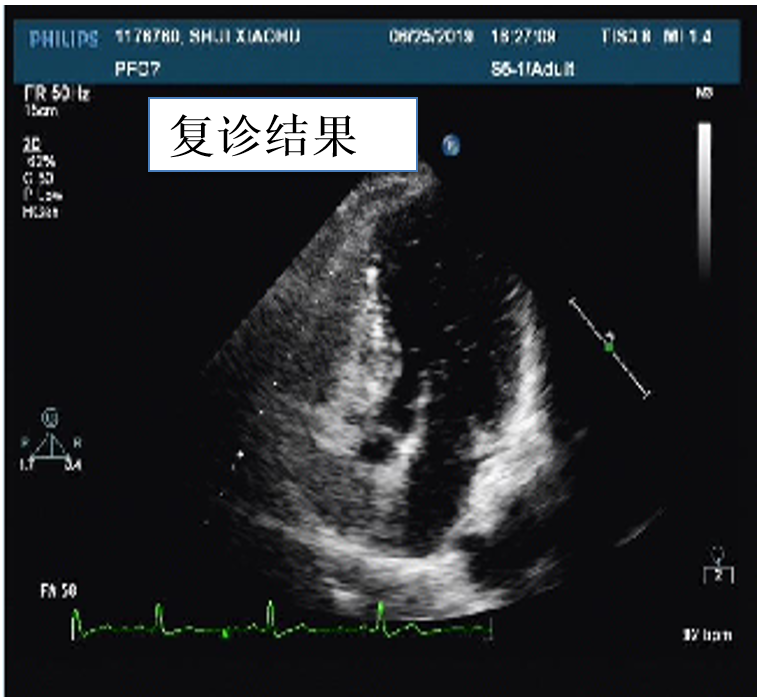

随访结果

2020年08年04日来我院进行手术后复诊,行心脏彩超

图片